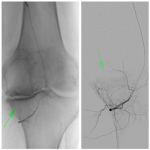

Embolización arterial selectiva

Hernán G. Bertoni, Victoria Bertoni, Carlos M. Autorino, Federico Manfrin